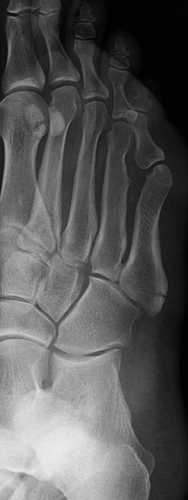

• Fracture of the base of the fifth metatarsal, at least 1.5 cm. distal to the metatarsal styloid.

• It can be confused with an unfused apophysis of the fifth metatarsal. However, the apophysis is usually aligned lengthwise, while the fracture is transverse to the bone .

• It can also be confused with an avulsion fracture of the styloid due to contraction of the peroneus brevis muscle, usually occurring closer to the metatarsal styloid.

• The image on the left below shows a Jones fracture that was fixed with a screw to aid healing. The image on the right is an avulsion fracture.